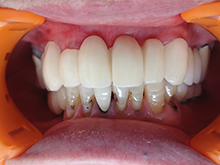

ハイブリッドセラミックス

ハイブリッドセラミックスとはセラミック粒子を92%含有した白い材料で、セラミックスのもつ審美性と耐久性、

より天然歯に近い硬さの材料です。

症 例